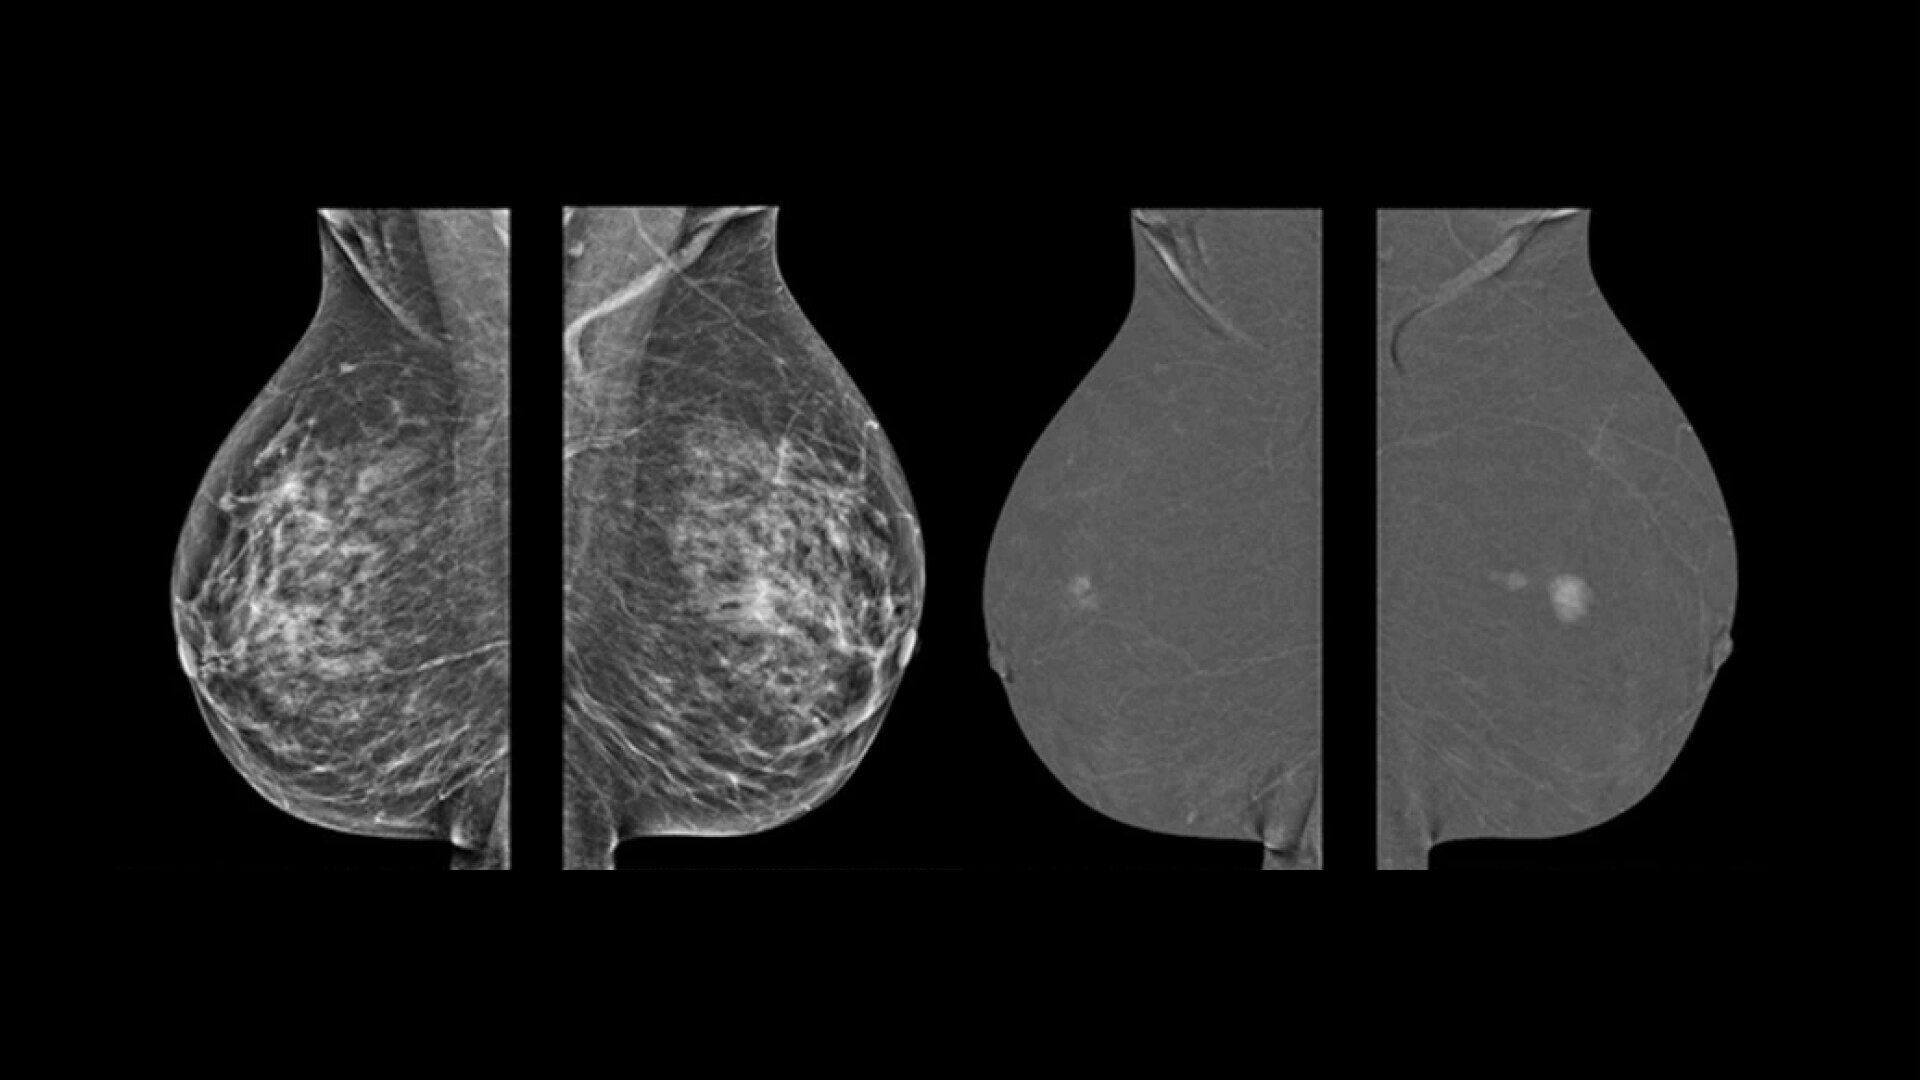

• Find lesions that cannot be seen on routine mammography6,7,8.

• Provide high specificity for low false-positives1.

• With Nira, overall Image quality was better assessed in more than 98% of the images presented by all the readers9.